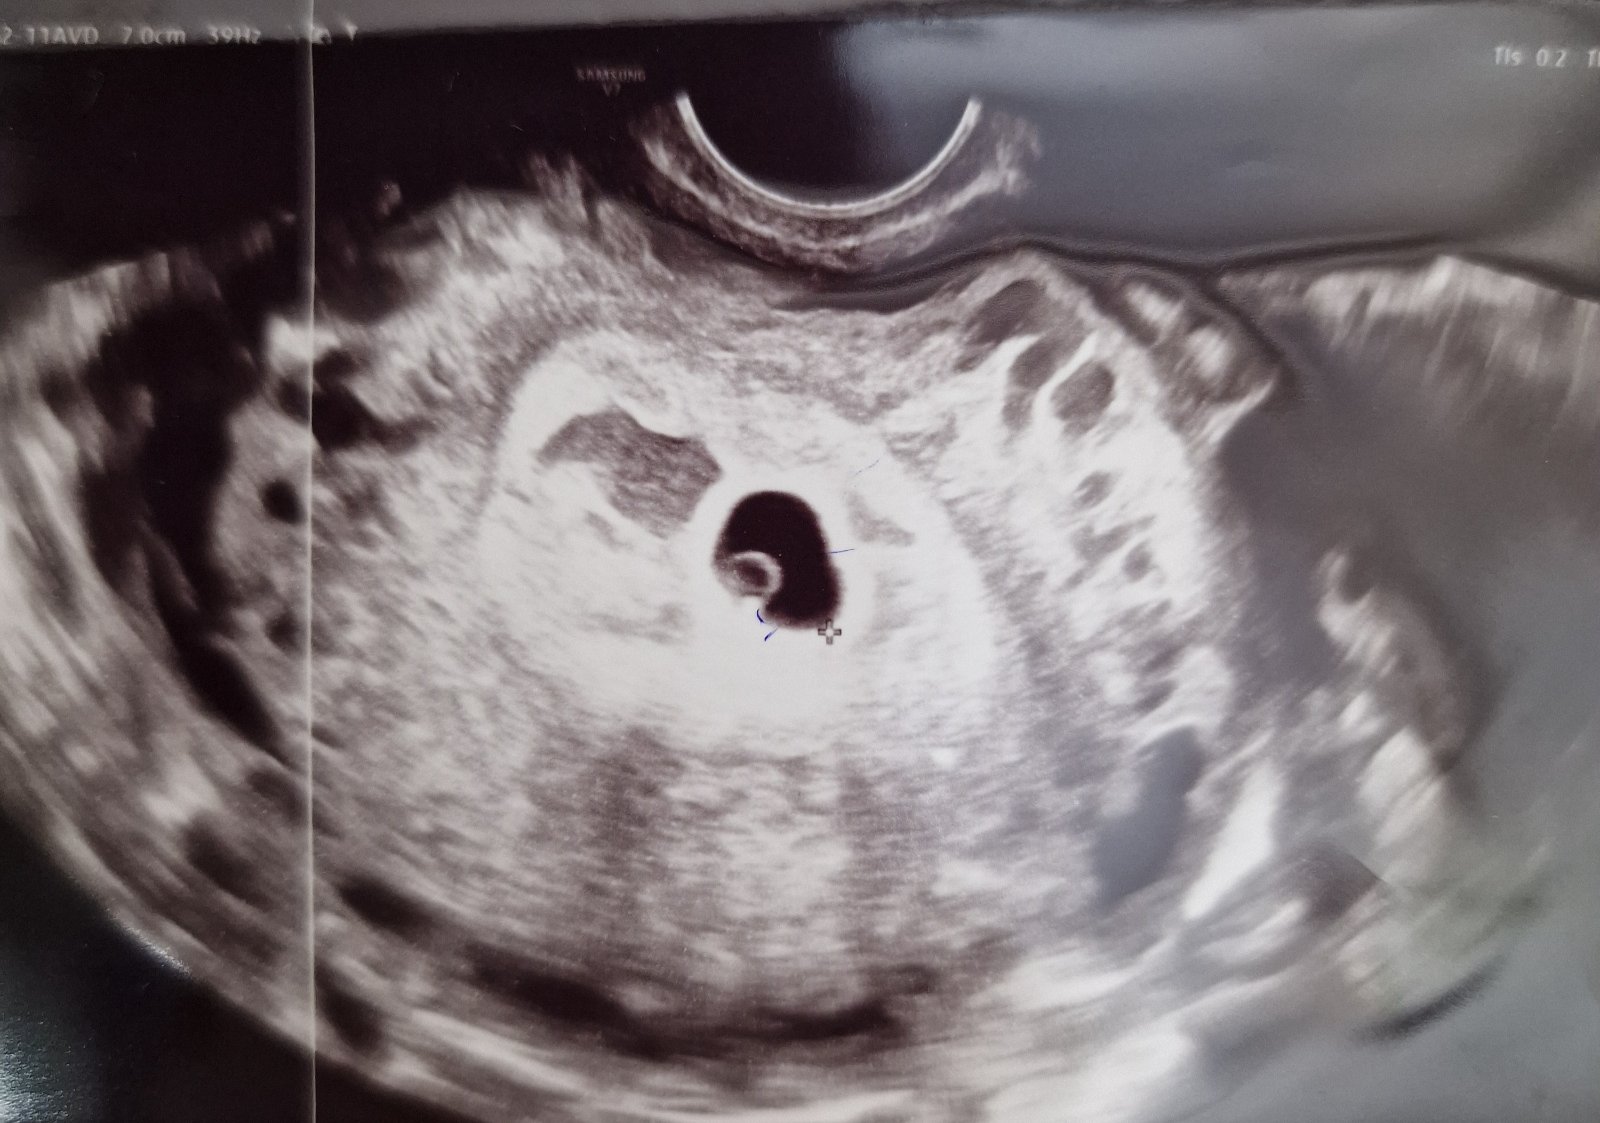

Čo vidieť na ultrazvuku v 5. týždni tehotenstva?

Dobrý deň prosím vás bol niekto v 5tt+3 dni ku Gynekológovi? Bolo niečo vidieť už? Rada budem ked sa podelite somnou o foto sona v takom týždni ked ste boli 😊

Nebud vystresovana ak nebude vela vidiet, v tomto case staci dutinka lokalizovana v maternici ( teda sa vyluci mimomaternicove) a v dutinke uz by mohli byt embryonalne struktury. Srdiecko sa potvrdzuje okolo 8 tyzdna. Samozrejme vsetko zalezi kedy bola ovulacia, par dni rozdiel hore dolu a uvz vyzera uplne inak.

To je krasny uvz - dutinka a nieco v nej 🙂 neskorsie myslel ze menej? To je ok, ovulacia mohla byt par dni neskor, spermie vedia pockat 🙂

Nabuduce uvz sa yz moze ukazat srdiecko